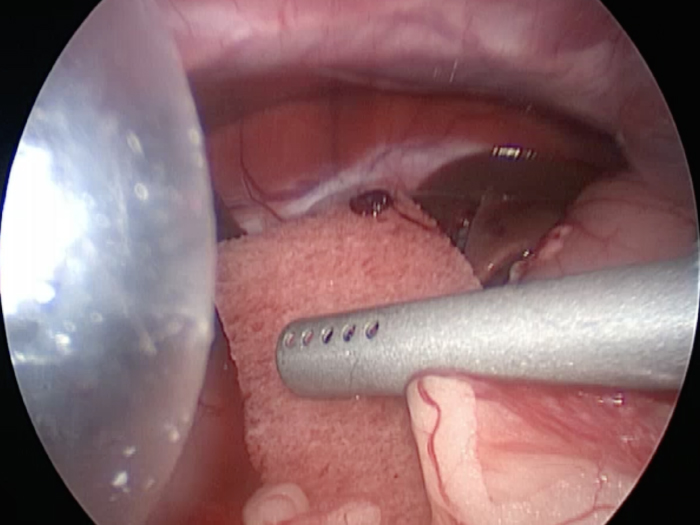

胆嚢の通路がちゃんと開通しているのか調べるために造影検査をしています。

この処置をすることで洗浄の効果と詰まりを確認することができます。

体の外に出すためお腹の中で袋に入れていきます。

このときに胆嚢と一緒にクリップやガーゼも回収します。

そしてお腹の中をきれいにしていきます。

最後にお腹の中をきれいに洗浄していきます。

胆嚢の頸部に糸を通し動脈を確保しています。

総胆洗浄をして詰まりがないかまずは確認します。(右)

きれいに開通していました。鉗子が大きく感じますが体が小さいので大きく見えます。